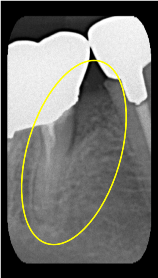

垂直性骨吸収+α-TCP

Perio Wave +Er:YAGレーザー+コールドレーザーの例です。

Perio Wave+Er:YAGレーザー+コールドレーザーで治療した箇所の経過です。

左から直後、1ヶ月経過時、2ヶ月経過時の画像です。